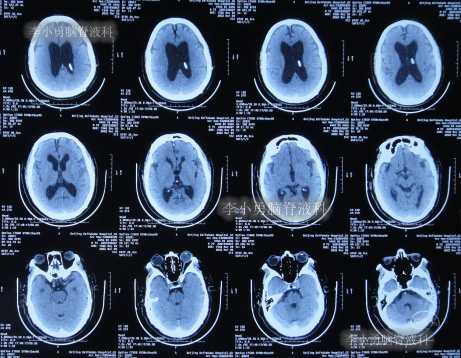

发现脑积水后8天即2020年11月6日,就诊于第2家的上海的某三甲医院,入院后再次检查(图-2)后诊断为正常压力脑积水。

图-2:2020年11月11日头部核磁